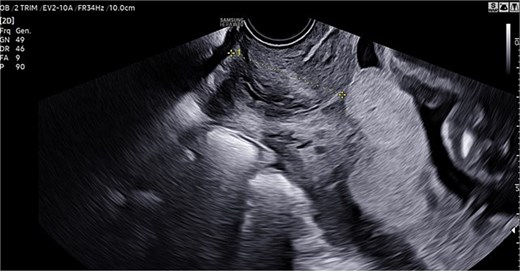

A 46-year-old woman underwent in vitro fertilization (IVF). Pregnancy progressed normally, with physiological development and appropriate fetal growth. In the third trimester, an ultrasound confirmed the diagnosis of a central PP (Fig. 1).